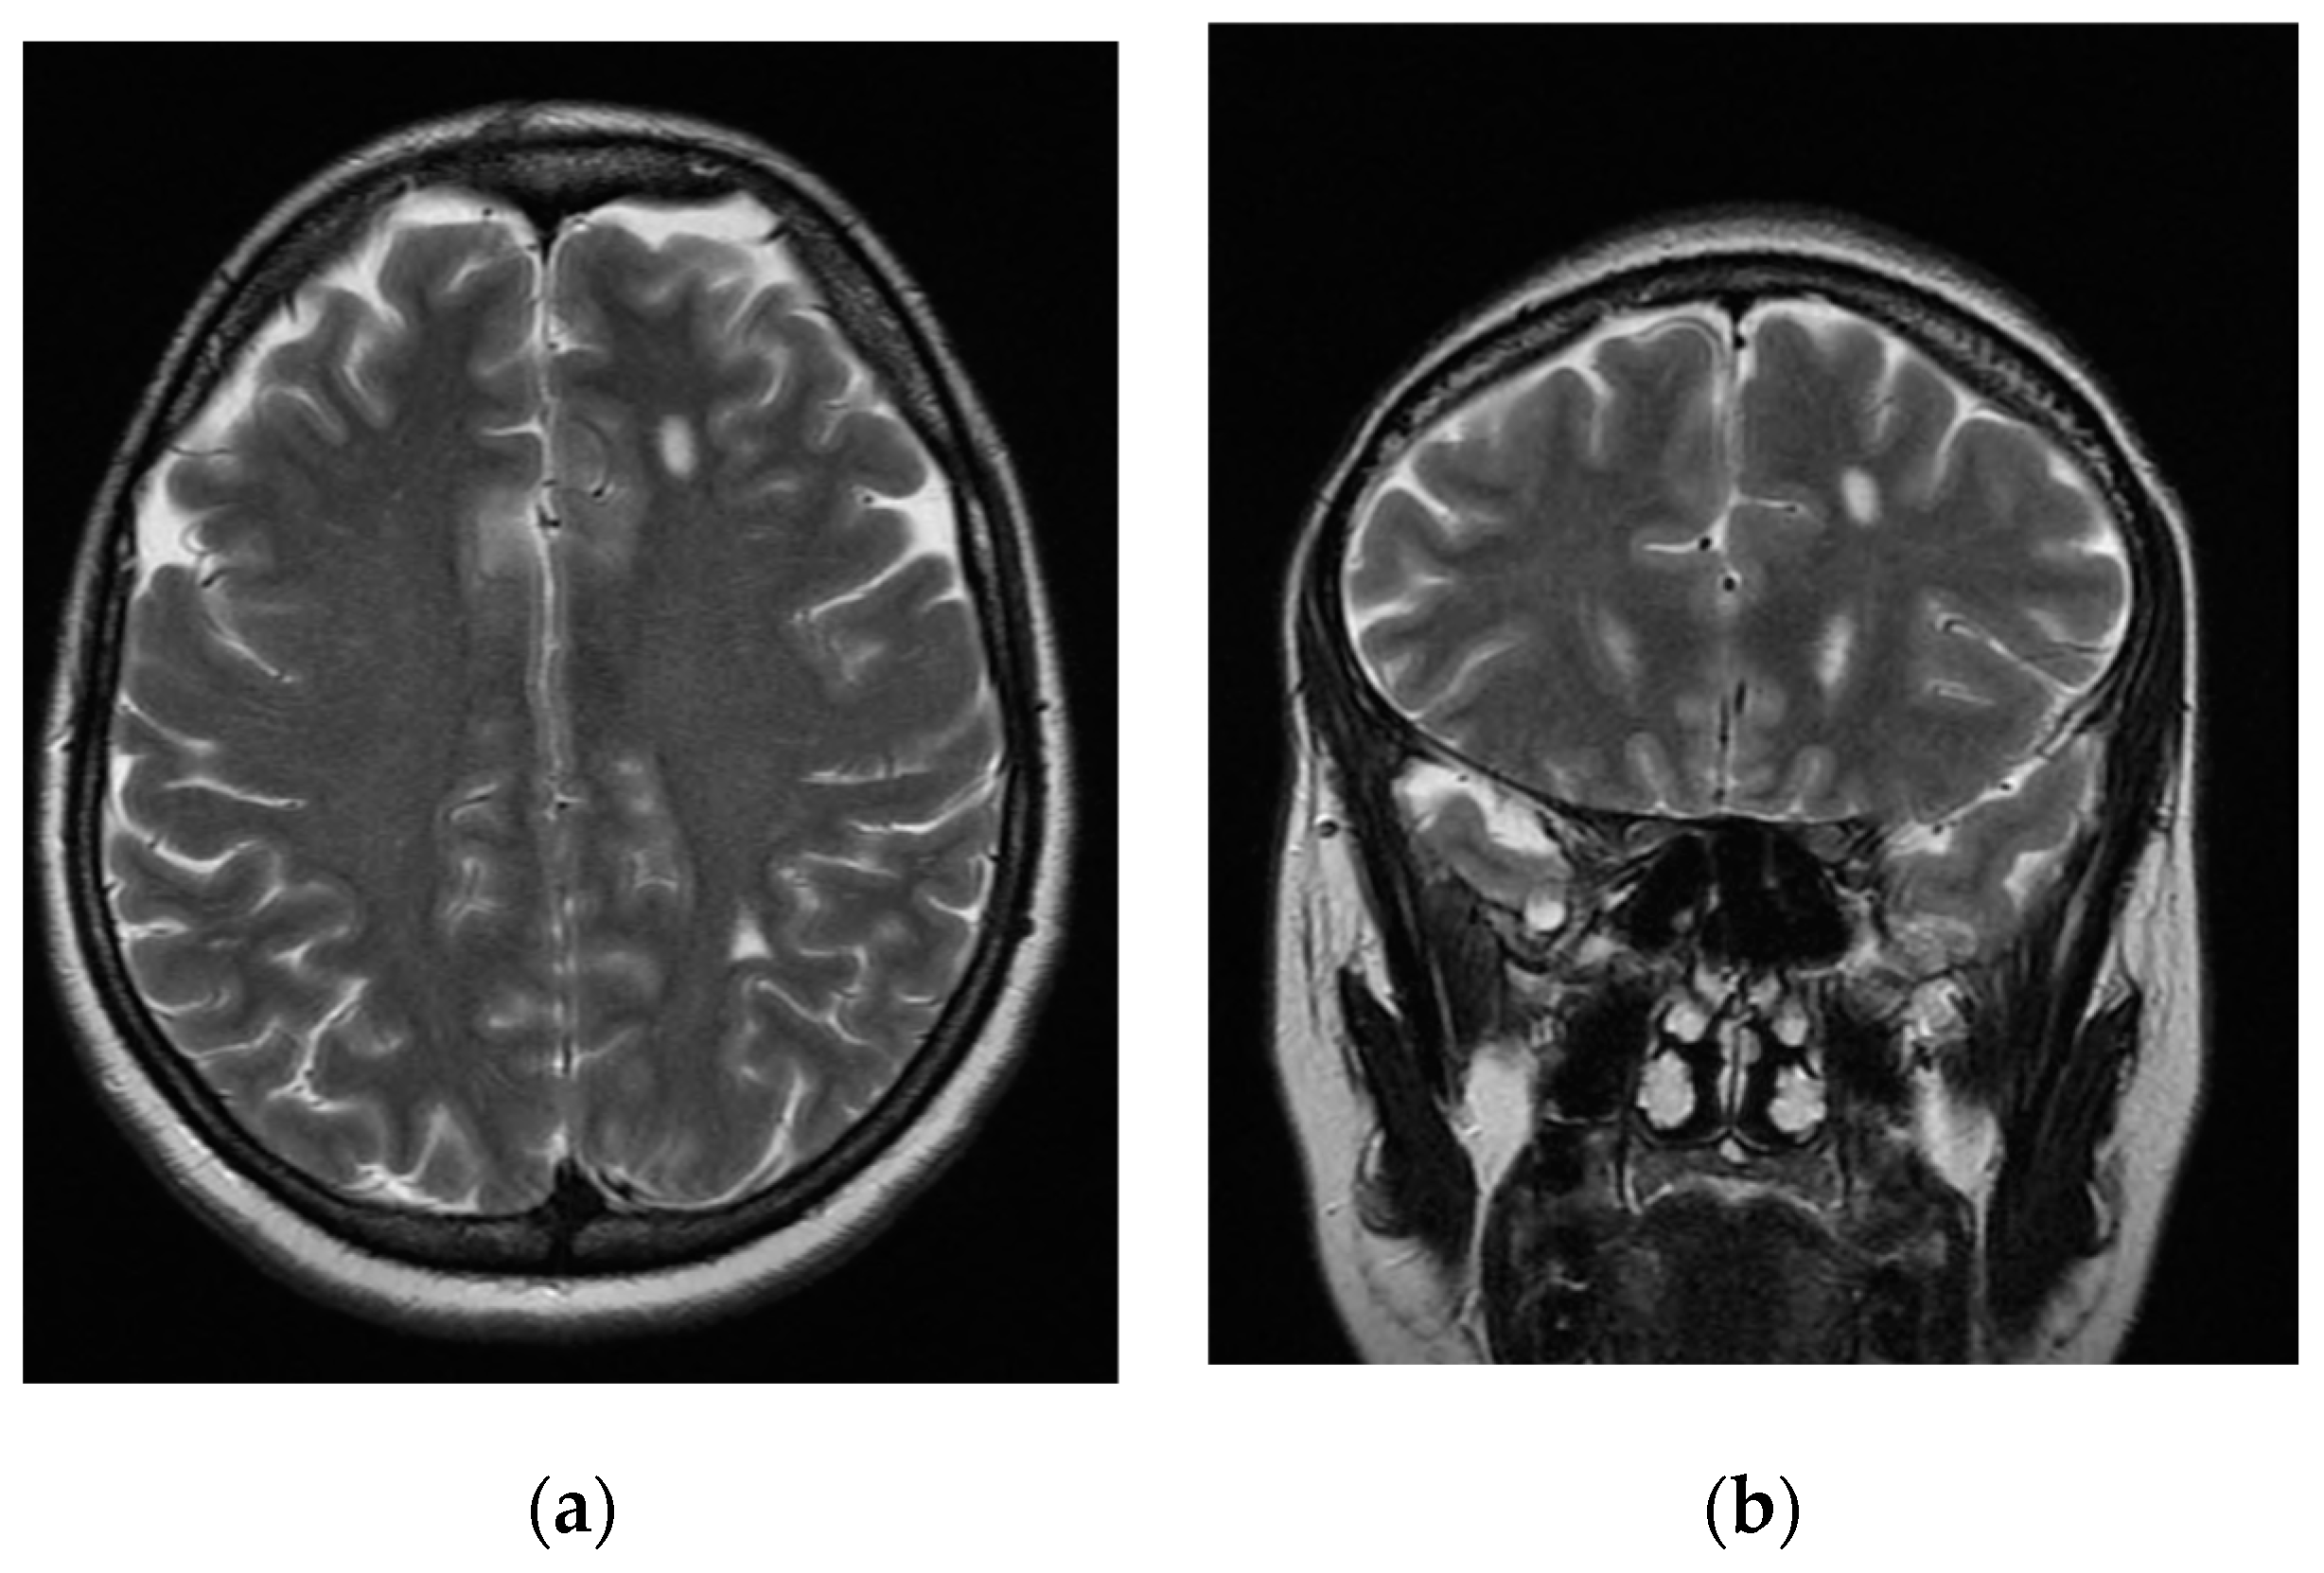

| Vilos et al., 2011 [43] | 41 | Chronic pelvic pain, menorrhagia, dysmenorrhea, and myoma; 3 caesarean births; tubal ligation | Sensory motory abnormalities, pains on the face, paroxysmal headaches, focal seizures | CT, MRI, EEG | Circumscribed abnormality in the centrum semiovale | 1 brain lesion without significant gadolinium enhancement on MRI; no abnormalities on EEG | No | Yes | Endometrial balloon ablation, GnRH-a, antiepileptics, salpingo-oophorectomy | Yes |